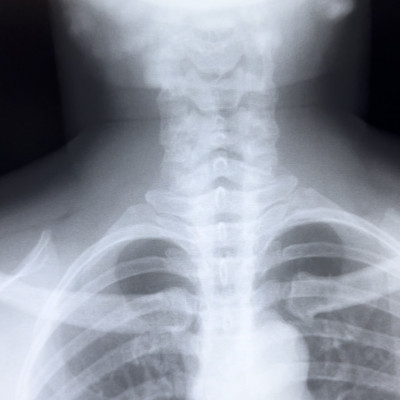

I had not thought much about radiology before; I think largely because I didn’t know exactly what that entailed. After speaking with Dr. Eric, a radiologist at Ridge, I learned a lot more about radiology that piqued my interest. Before going to observe, he gave us a general overview of the department. He explained how there are two categories of practice—the technical side and the diagnostic side. The technical side includes the practice of capturing the images and ensuring that they are high quality. The diagnostic side entails just that, analyzing the images to come up with a diagnosis or conclusion for the case. Both are essential for the performance of radiology. I also learned about the different methods that are used in interventional radiology: x-ray, fluoroscopy, CT scans, MRI, and ultrasounds. I did not know the difference between CT scans and MRI, or that running an MRI machine costs much more than a CT scan.

Another day at Level 2 Surgery! Today, I got to see ortho, plastics, and caught about 10 seconds of an eye surgery before walking out of that OR. As my time at Ridge goes on, I’ve been learning a lot about my own preferences, which has been incredibly helpful in figuring out what I like and what I definitely don’t see myself doing. Ortho was fascinating to watch, but seeing the bone, using the saw, and the full exposure of major areas during surgery made me realize that I could not see myself doing that. But I got a full learning experience because the scrub tech, Clifford, and the surgeons were so open to our questions. We learned about Intertrochanteric Fracture and saw the X-ray scan for that. They were going to do DHS surgery, a procedure used to stabilize and fix a fractured hip with an artificial screw.